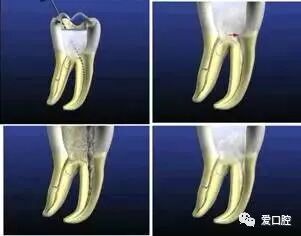

( 1 )定义:弯曲根管根尖拉直造成根尖位置的改变。

出现台阶可造成根尖拉开,根管治疗需进行根管填充时根管三维充填占满困难。

( 2 )原因:器械没有预弯,弯曲根管过多使用旋转力。

根管治疗时插入困难,采取硬顶的方法易造成根尖拉开,出现台阶。根管治疗时器械插入困难正确的方法更换更细小的器械,轻轻探查,预弯。

( 4 )解决方法: 1 )器械预弯。2 )短距离,上下提拉法扩锉。3 )不要旋转器械或改变其倾向。4 )勿使用直且粗的锉预备弯曲根管。

( 1 )定义:根管侧壁过度切削过薄以至穿孔。

( 2 )原因:根中区域的过度切削,特别是上颌磨牙的近中颊根和下颌磨牙的近中根 。

牙胶尖什么颜色根管治疗的标准步骤以及治疗细节的把握_https://www.jmylbn.com_新闻资讯_第32张